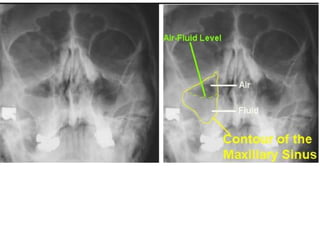

2.Sinusitis: paranasal air sinuses may

Maxillary sinusitis is commonest